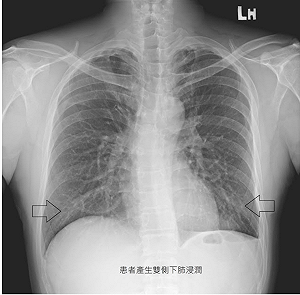

壯漢用電子煙戒菸變病貓! 蘇一峰:3個月內肺活量少4成